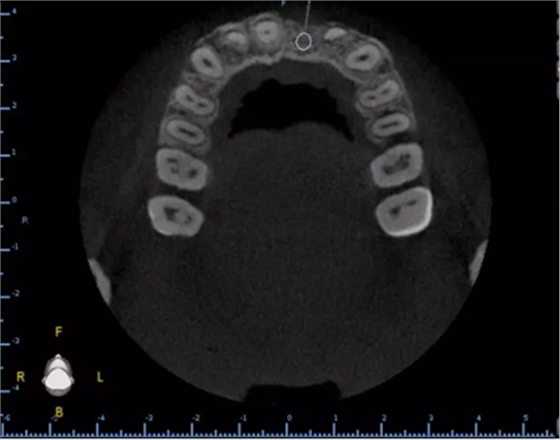

1.術(shù)前CT

2.術(shù)前植體設(shè)計(jì)